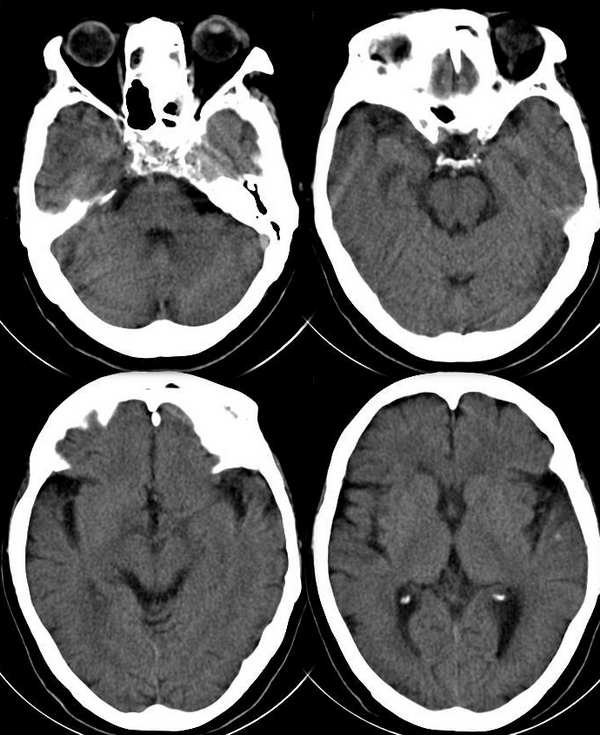

女,76岁,高血压病史二十余年。8小时前出现头晕,呕吐。无神经系统体征

基本不考虑出血!好象有鼻窦炎,向下加一个层面就好了。

不象是出血,请薄层扫描颅底,斜坡似乎有问题,左侧筛窦炎?